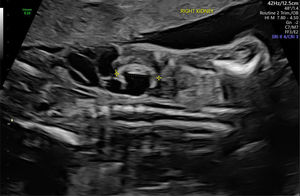

Figura 2.Displasia obstructiva alrededor de las 20 semanas de edad gestacional. Este feto masculino mostraba una obstrucción del tracto urinario inferior con riñones ecogénicos e hidrouréter severo; en esta imagen se visualiza y mide el riñón derecho. Imagen ecográfica del Centro Médico de la Universidad Erasmus.

El diagnóstico diferencial de DTU depende en gran medida de la localización y del grado de dilatación dentro del tracto urinario. La hidronefrosis sin hidrouréter puede indicar una obstrucción de la unión pieloureteral (UPU) (fig. 4), mientras que la dilatación de la pelvis renal con hidrouréter sugiere más probablemente un reflujo vesicoureteral (RVU) o una obstrucción de la unión vesicoureteral (fig. 5). Además, una hidronefrosis severa puede, en ocasiones, simular RDMQ; por lo tanto, este último debe incluirse en el diagnóstico diferencial. Dado que un sistema colector renal duplicado puede asociarse con hidronefrosis en una o ambas porciones, se recomienda una evaluación detallada del aspecto renal y la búsqueda de un ureterocele en la vejiga. La dilatación de todo el sistema (riñón, uréter y vejiga) indica una obstrucción congénita del tracto urinario inferior (fig. 6), que puede tener diversas etiologías, como válvulas de uretra posterior (en fetos masculinos), atresia uretral o malformaciones cloacales (en fetos femeninos)19. Con excepción de la pielectasia transitoria, siempre se ofrece evaluación genética prenatal ante la sospecha de DTU fetal.

Obstrucción del tracto urinario inferior alrededor de las 23 semanas de edad gestacional. Obsérvese la hidronefrosis bilateral, más prominente en uno de los dos riñones. La vejiga también está agrandada (no visible en esta imagen). Imagen ecográfica del Centro Médico de la Universidad Erasmus.